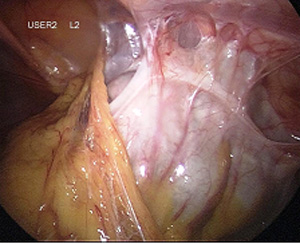

Myome, die sich in der Gebärmutterwand (intramural) oder auf der Außenseite (subserös) des Uterus befinden, können in aller Regel per Bauchspiegelung entfernt werden, dabei wird ein sogenanntes Laparoskop durch den Bauchnabel geführt. Verbunden mit einem Kamerasystem ermöglicht es dem Operateur im Bauch "sehen" zu können. Mit zwei bis drei zusätzlichen Instrumenten können die Myome mittels minimal-invasiver Operationstechnik aus der Gebärmutter "herausgeschält" und entfernt werden. Die Gebärmutter wird dann wieder vernäht. Vor einer eventuell geplanten Schwangerschaft wird empfohlen, einen Zeitraum von drei bis sechs Monaten abzuwarten. Die Technik der Laparoskopie ermöglicht es, die mit einem Bauchschnitt verbundenen Schmerzen zu vermeiden - dennoch kann es unter Umständen sinnvoll sein, sehr große oder ungünstig gelegene Myome, durch einen Bauchschnitt zu entfernen